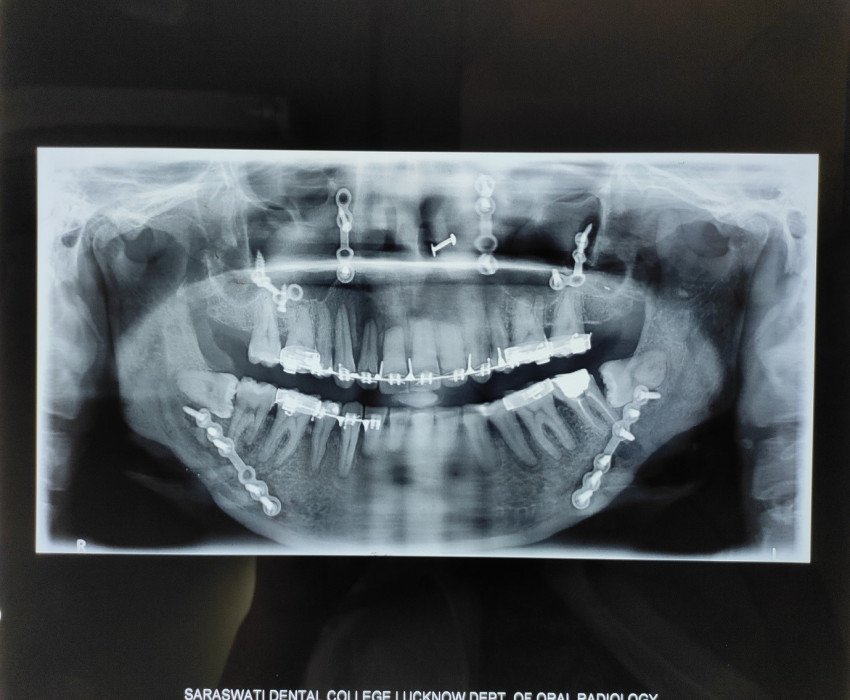

Orthognathic surgery may help to correct problems with swallowing or speech, correct bite fit or jaw closure issues, correct facial asymmetry, relieve pain caused by temporomandibular joint (TMJ) disorder, repair facial injury or birth defects and provide relief for obstructive sleep apnoea.

Surgery on the upper jaw may be performed to correct receded or protruding upper jaw, crossbite, abnormal teeth display during smile, open bite or reduced growth of the middle of the face. Whereas, the surgery on the lower jaw may be performed to correct a receding or protruding lower jaw and to correct any chin deformity.

Orthodontists work hand in hand with oral and maxillofacial surgeons and through the surgery, it is possible to place the teeth and jaws in a more attractive, functional, and healthy position.